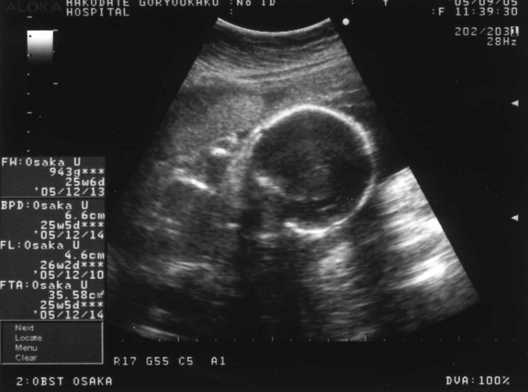

Feb 11, · 26週目出産に向けて取り組んだこと 旦那の妊娠日誌 期限的にそろそろ 産婦人科 で開催されている教室に参加したほうが良さそうです(教室が月に1回程度しか開催されないため)Nov 16, · 妊娠26週目の胎児の体重 26週目の胎動 26週目の血糖値 一般的な1型糖尿病妊婦の血糖値の変動は? つわりのぶり返し 抜け毛が・・ 妊娠26週目の胎児の体重 26週目です。検診を受けて、胎児は今850gだそうです‼️大きさも大丈夫らしい( ´ ` ) 26週目の胎動 とてつもなく動きます。先日、欧州ではマツダコネクトのApple CarPlay / AndroidAuto対応について発表がありました。そろそろ北米でも18 Mazda6に対してのアップデ

10 妊娠中期の検査・妊婦検診8回目(26週6日)~性別確定編~ ブログ内検索 結構いろいろ書いてます。Let's search!(^^)vSep 12, 17 · 妊娠26週は妊娠7ヶ月の最終週です。妊娠7ヶ月から健診の回数が2週に1回になり、より頻繁にエコー写真を見る機会が増えることでしょう。赤ちゃんの性別がわかるようになり、出産準備にもそろそろ本腰をいれる頃です。体重も増え、大きくなったお腹で移動するのは大変ですが、赤妊娠26週目に下腹部の痛みや不快感を感じたら、 ママの子宮内の羊水の量を超音波検査(エコー検査)で調べてもらいましょう。 妊娠26週目ママの症状 骨盤の痛み:出産に備えてママの骨盤の靱帯が緩み、柔らかくなっていきます。椅子に座ったり椅子

572gで誕生した我が子 26週 いつもの定期検診のはずが緊急帝王切開に ゼクシィbaby 妊娠 出産 育児 みんなの体験記